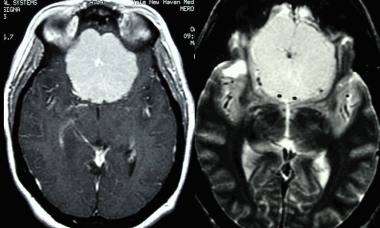

Метастазы головного мозга на МРТ. Фото. Определяются множественные метастазы в мозг при раке легкого: слева в режиме Т1-ВИ в виде гипоинтенсивных образований, справа — в режиме Т2-ВИ виде множественных участков повышенного сигнала, окруженных зоной перифокального отека. У пациента подтверждена первичная опухоль легкого.

Отдельно необходимо рассмотреть МР-признаки метастазов меланомы в головной мозг, которые обладают сигнальными характеристиками, отличающимися от других опухолей вследствие наличия меланина в структуре. Метастазы безамилоидной меланомы выглядят на МРТ аналогично метастазам других опухолей, описанным выше. На Т1-ВИ они имеют резко гиперинтенсивный (высокий, яркий) сигнал, а наТ2-ВИ — изо- либо гипоинтенсивный (пониженный) сигнал.